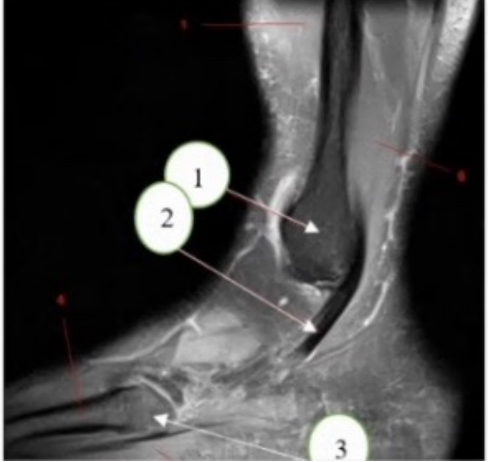

What anatomy is arrow 1 is pointing at?

a. Tibia

b. Fibula

c. Talus

What anatomy is arrow 2 is pointing at?

a. Pealajurti tendon

b. Peroneal tendon

c achillies tendon

d. Tibialis tendon

What anatomy is arrow 3 is pointing at?

a. 15 metacarpal tuberosity

b. 5 metatarsal tuberosity

C 15 melatarsal tuberosity